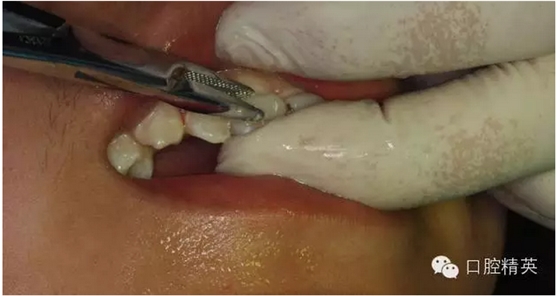

圖12.局部浸潤(rùn)麻醉

圖13.清理21牙槽窩

圖14.再植21離體牙

圖15.縫合初固定21